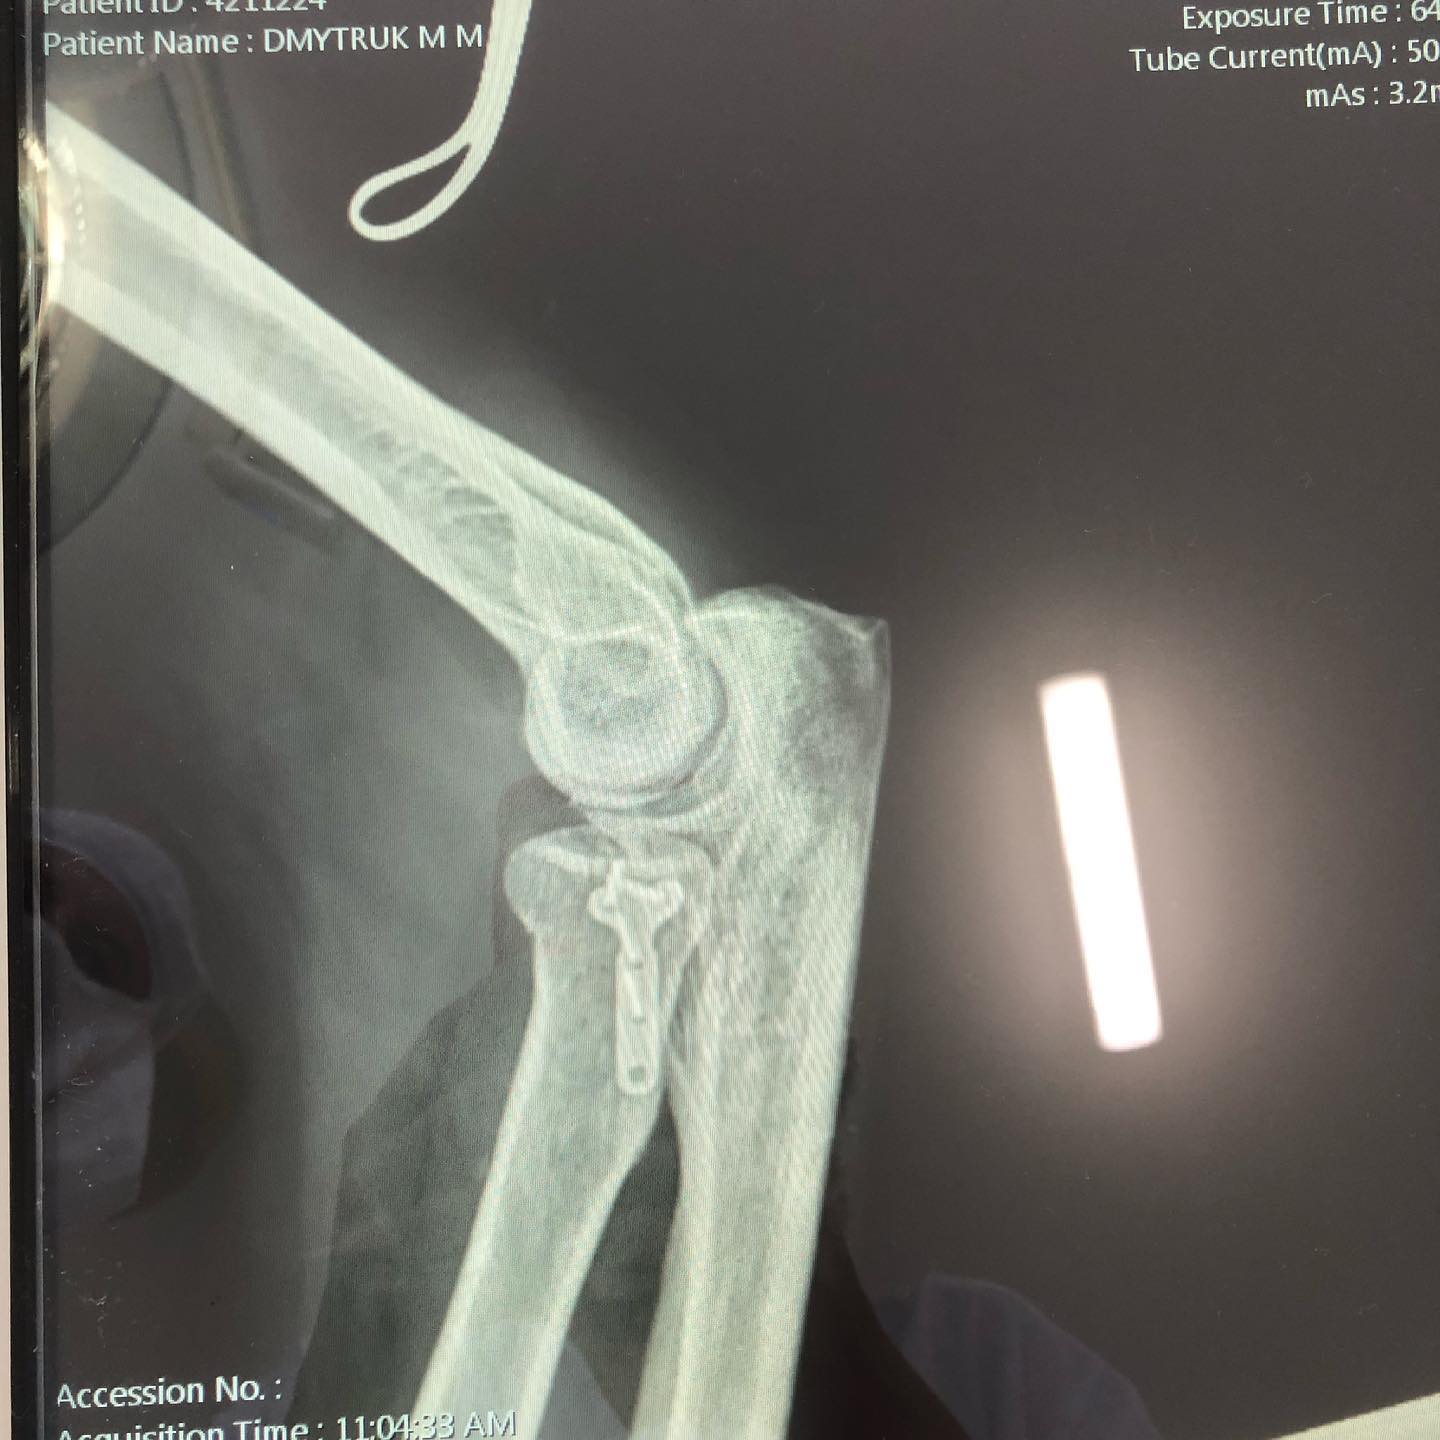

У Нововолинській центральній міській лікарні медики успішно прооперували пацієнта, у якого була зламана рука.

Відомо, що чоловік під час гри у теніс впав на випрямлену руку. Відчувши сильний біль, він одразу звернувся в приймальне відділення лікарні, де отримав ургентну медичну допомогу.

Після проведеного обстеження пацієнту встановили діагноз: перелом голівки променевої кістки. Хворого медики успішно прооперували.